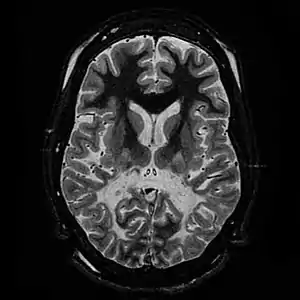

| T2 weighted axial scan of a human brain at the level of the caudate heads demonstrates marked loss of posterior white matter, with reduced volume and increased signal intensity. The anterior white matter is spared. Features are consistent with X-linked adrenoleukodystrophy. | |